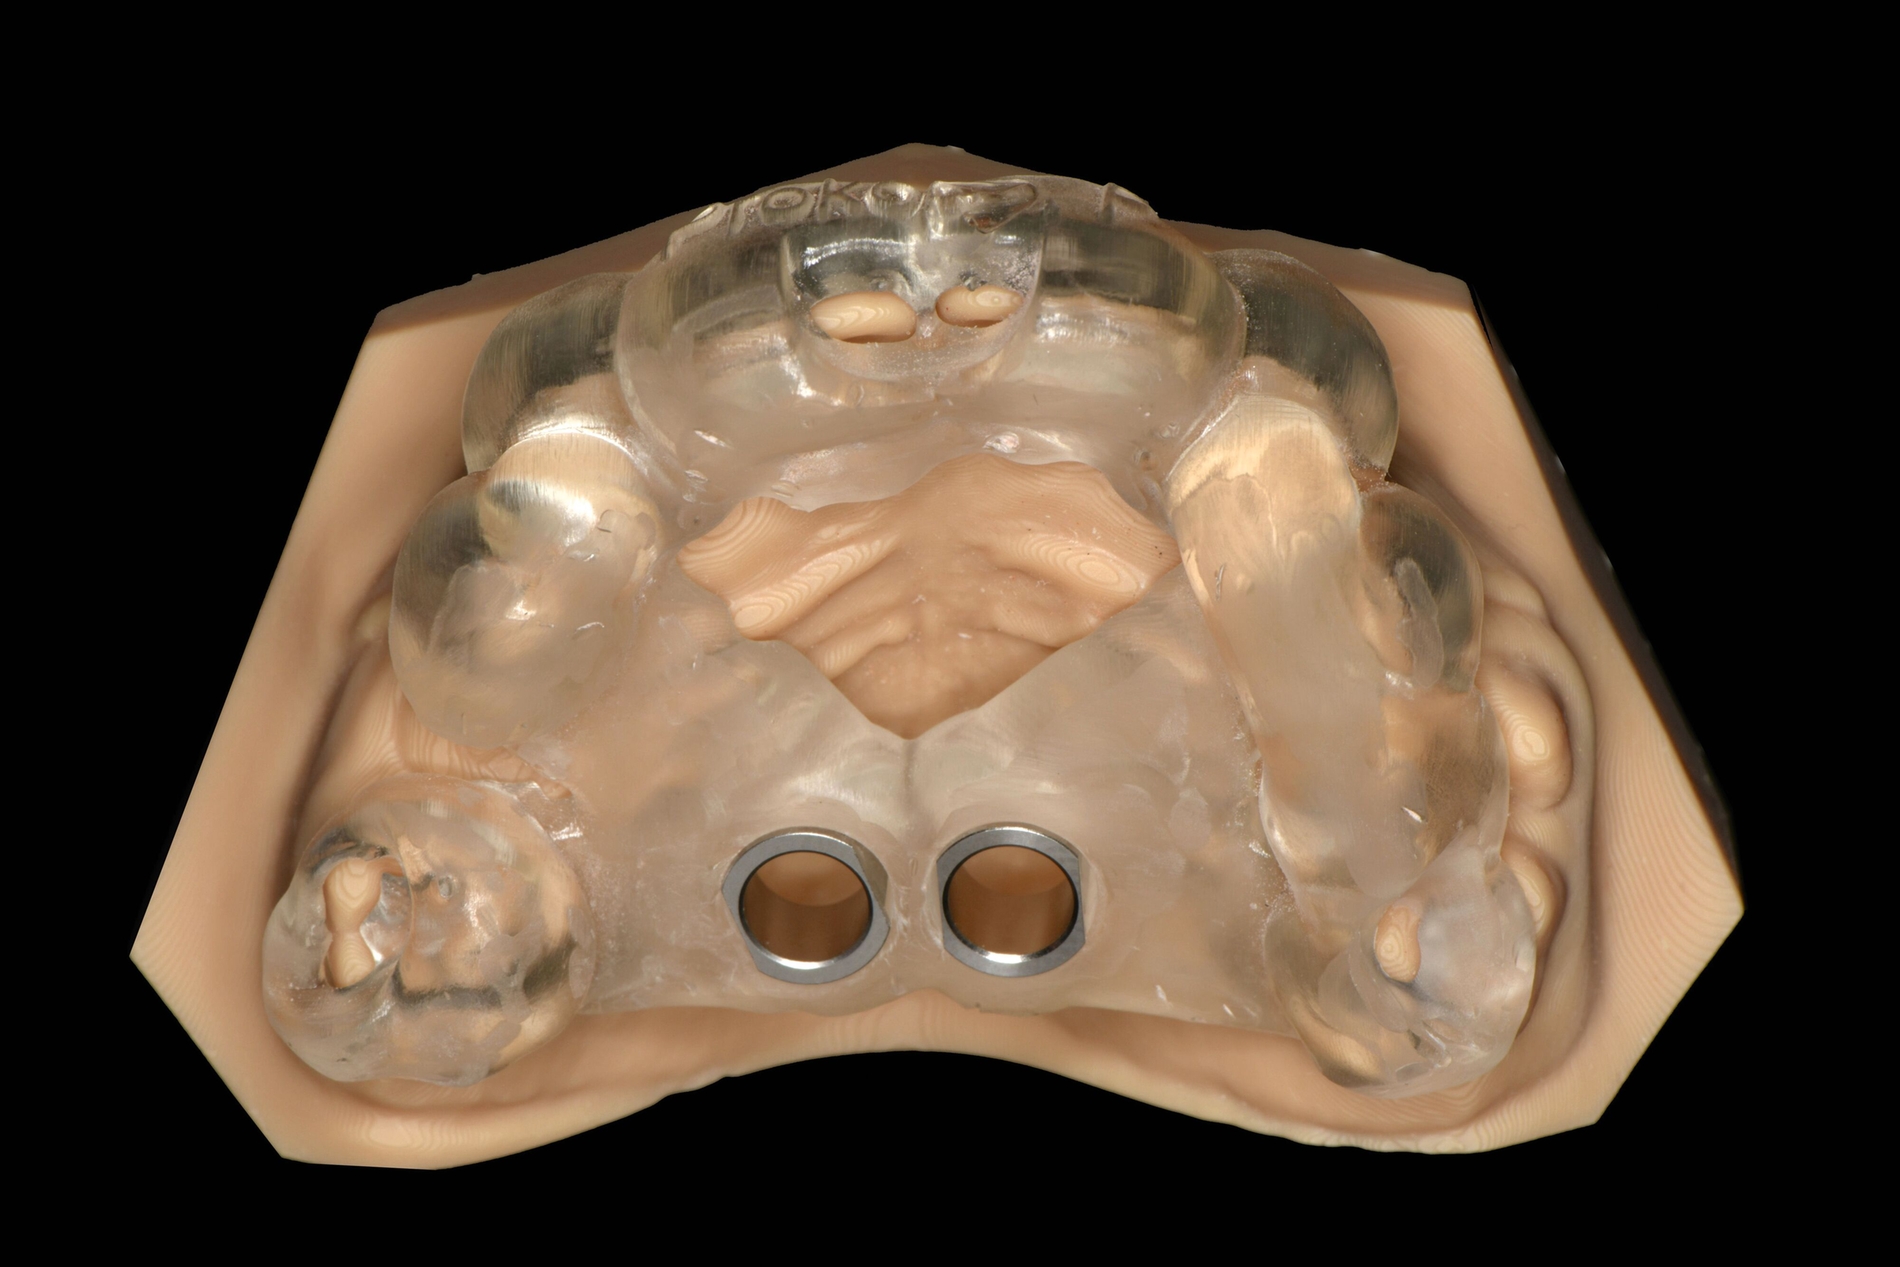

Design und Herstellung der CAD/CAM-Bohrschablone

Initial wurde ein Intraoralscan (IOS) des Oberkiefers durchgeführt. Des Weiteren erfolgte eine DVT zur dreidimensionalen Lagebestimmung der Zahnkeime. Die Daten des IOS des Oberkiefers und der DICOM-Datensatz der DVT wurden in die Planungs-Software (coDiagnostiXTM, Dental Wings GmbH, Chemnitz) importiert. Nach Überlagerung der Datensätze erfolgte die Festlegung der Positionen der Mini-Implantate, um eine Schädigung der verlagerten Zahnkeime zu vermeiden. Nach dem virtuellen Design der dental gelagerten Bohrschablone wurde diese als Standard Tessellation Language (STL)-Datei exportiert.

Die Herstellung der Bohrschablone erfolgte additiv mittels Stereolithographie (SLA) Vat-3D-Drucker. Das verwendete biokompatible und autoklavierbare Material wurde in einer Schichtdicke von 100 µm gedruckt, die sich in einer früheren Studie als suffizient erwiesen hatte [Aretxabaleta et al., 2021]. Die Finalisierung der Bohrschablone erfolgte nach den Herstellerangaben. Zur präoperativen Kontrolle der Bohrschablone wurde zusätzlich ein Oberkiefermodell additiv hergestellt und die Passung der Schablone kontrolliert.

Die Zähne 36, 37, 46 und 47 wurden in Allgemeinanästhesie chirurgisch freigelegt. Zusätzlich wurden die beiden paramedianen Mini-Implantate (2 x 9 mm, Benefit System; PSM North America, Indio, CA) ohne Vorbohren mithilfe der zuvor hergestellten Schablone inseriert (Abbildung 3). Für die Platzierung der Mini-Implantate wurde ein Winkelschraubendreher verwendet. Direkt nach der Operation wurde die bmx DIRECT Hyrax-Schraube (10 mm, BENEfit®-System, Dentalline, Birkenfeld, Deutschland) an den Mini-Implantaten befestigt, um ein MARPE zu erzielen (Abbildung 4).